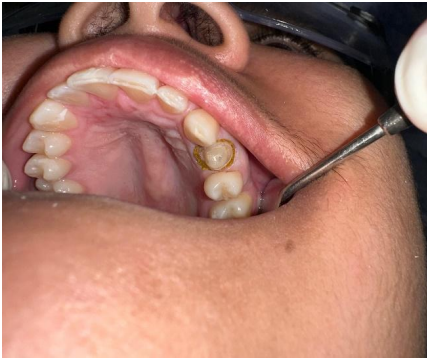

1ª Sessão: Inicialmente foi realizado a desubturação parcial dos canais radiculares, mantendo o selamento apical com o comprimento mínimo para garantir o sucesso endodôntico. Em seguida, foi realizada a prova e ajuste do pino de fibra de vidro, o qual apresentou boa adaptação, dessa forma, foi feita a anatomização dos condultos e cimentado com cimento resinoso dual, considerando o protocolo adesivo adequado: condicionamento ácido, aplicação dos adesivos compatíveis e inserção do cimento nos canais, garantindo o preenchimento adequado e ausência de bolhas, após essa etapa, foi realizada a fotoativação e fotopolimerização completa, o núcleo coronário foi preenchido com resina composta para criar um remanescente anatômico que possibilitasse a confecção do preparo. Na sequência foi realizado o preparo para receber a coroa total, respeitando os princípios da retenção, resistência e espessura do material. Para a moldagem funcional a gengiva foi afastada com o fio retrator, e executada com silicona de condensação (pesada e leve), garantindo a cópia fiel dos limites cervicais. Posteriormente foi confecciada uma coroa provisória em resina composta, devidamente com a oclusão ajustada e protocolos de polimento, proporcionando conforto, e estética satisfatória à paciente. A cor foi escolhida e o molde juntamente com o registro de mordida foram encaminhados ao laboratório para que fosse confeccionada a coroa de teste clínico, e na sequência a coroa definitiva.

Figura – Preparo do remanescente para receber a coroa